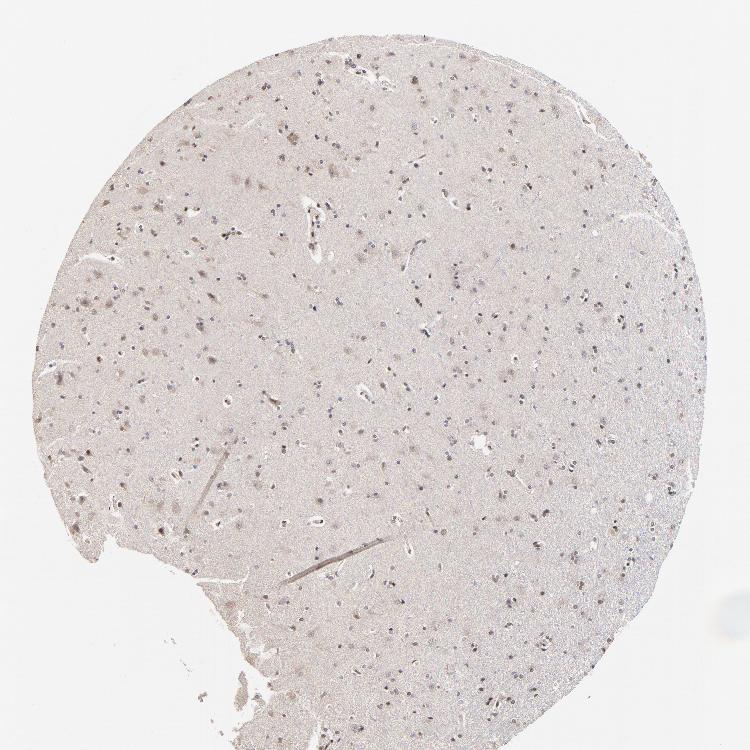

CEREBRAL CORTEX - Antibody stainingi

Antibody staining in the annotated cell types in the current human tissue is reported as not detected, low, medium, or high, based on conventional immunohistochemistry profiling in selected tissues. This score is based on the combination of the staining intensity and fraction of stained cells.

Each image is clickable and will lead to virtual microscopy that enables deeper exploration of all samples and also displays staining intensity scores, fraction scores and subcellular localization as well as patient and tissue information for each sample.

Antibody HPA002813

Endothelial cells Low

Glial cells Low

Neuronal cells Low

Neuropil Not detected